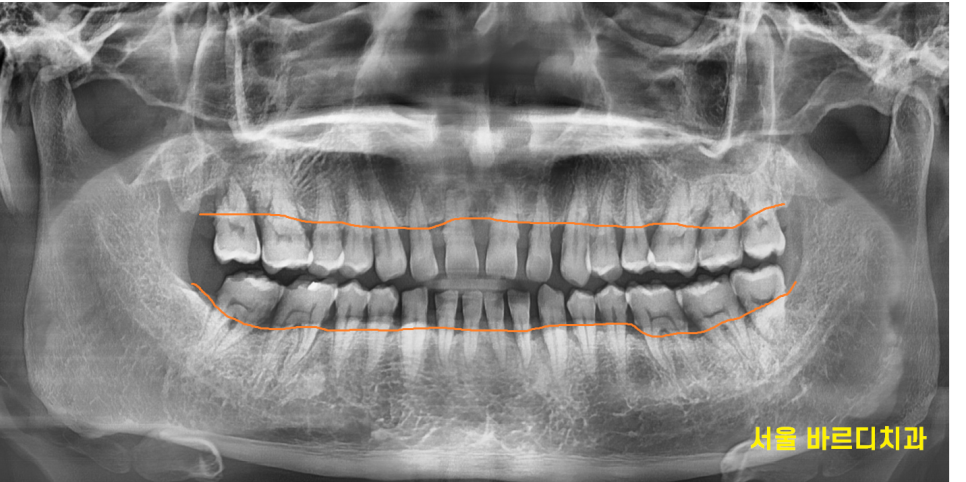

환자분도 전반적인 잇몸뼈 확인을 위하여 x ray를 찍어보았을 때

잇몸 뼈가 많이 내려간 상황이었습니다.

만성 치주염이 진행되고 있어

파노라마상에서도 공간이 잘 메꿔졌습니다~